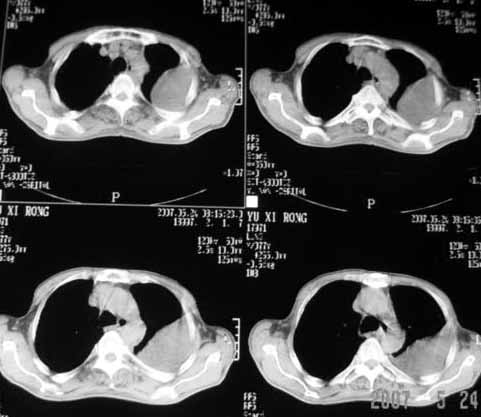

以下是引用luochengyi在2007-5-24 14:33:00的发言:[br]考虑左下肺癌。左侧胸腔积液。

以下是引用adams在2007-5-24 17:12:00的发言:[br]支持“考虑左下肺癌,左侧胸腔积液,建议胸水检查”。[br] [br]

以下是引用fumaogui在2007-5-24 16:20:00的发言:[br]左侧胸腔积液.[br]左下叶不张考虑中心型肺癌[br]建议纤支镜检查.